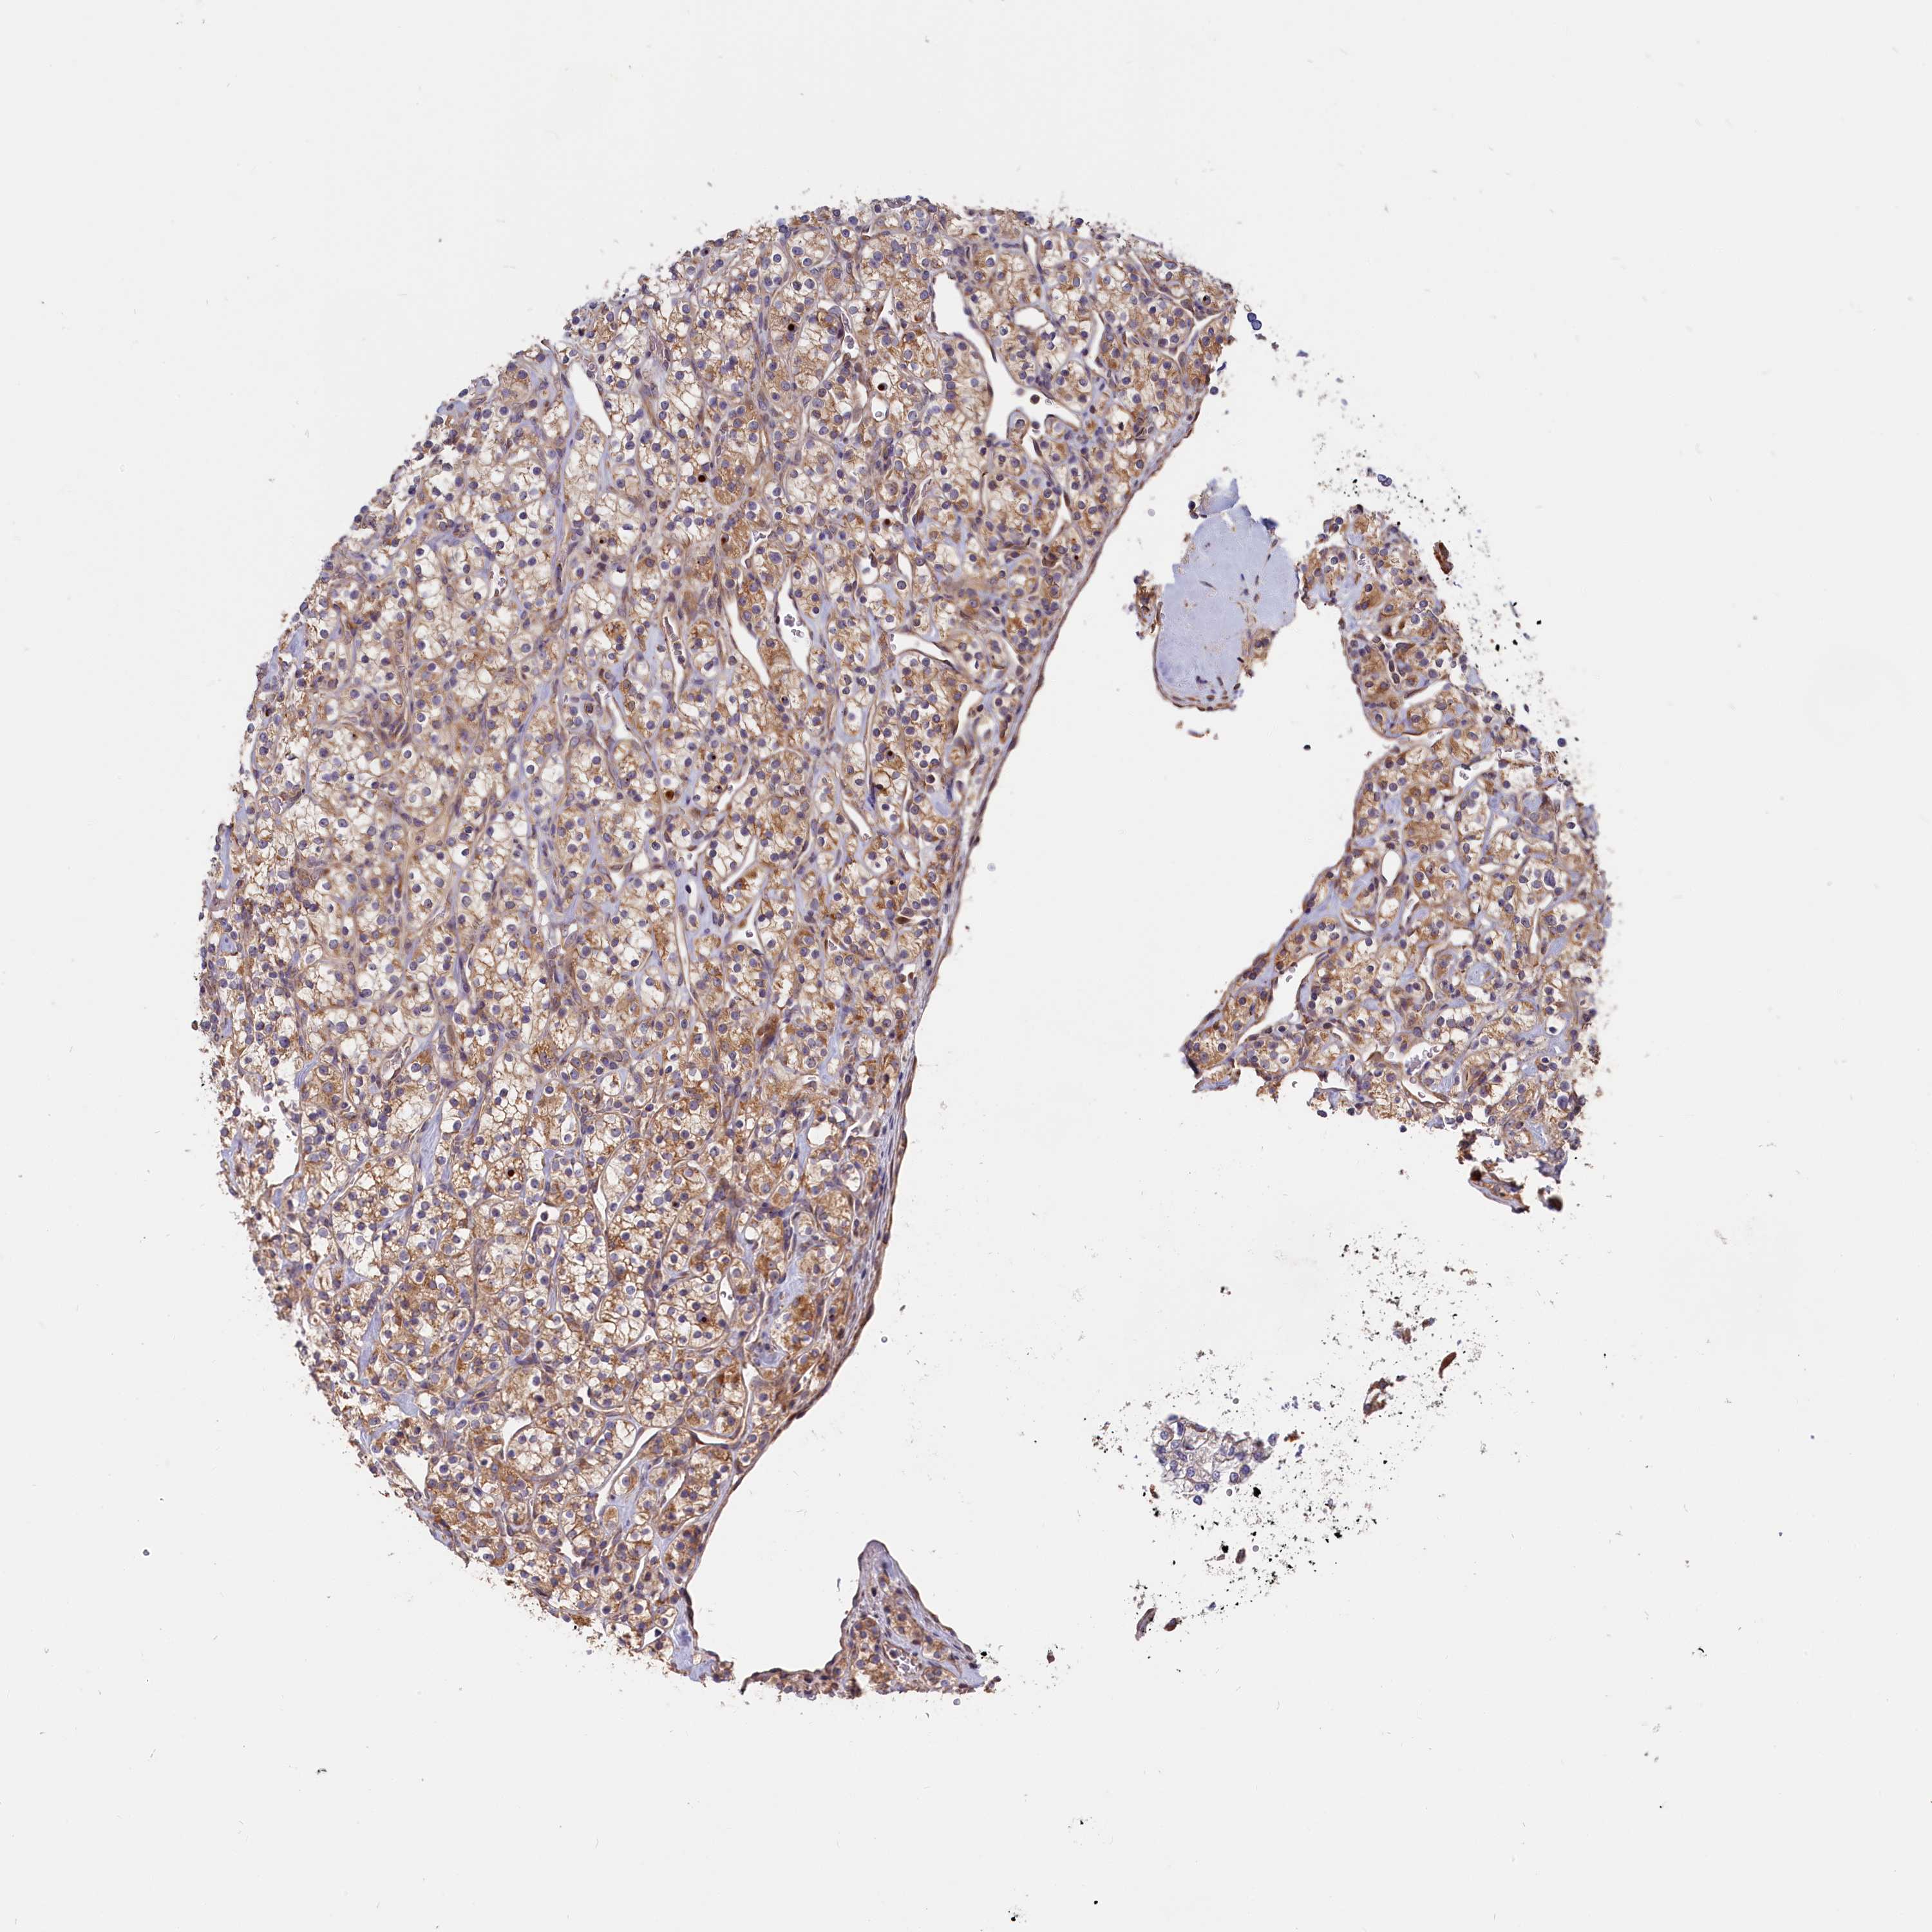

CANCER RENAL CANCER Show tissue menu

KICH TCGA KIRC TCGA KIRC VALIDATION KIRP TCGA PROTEIN RCC CPTAC PROTEIN EXPRESSION